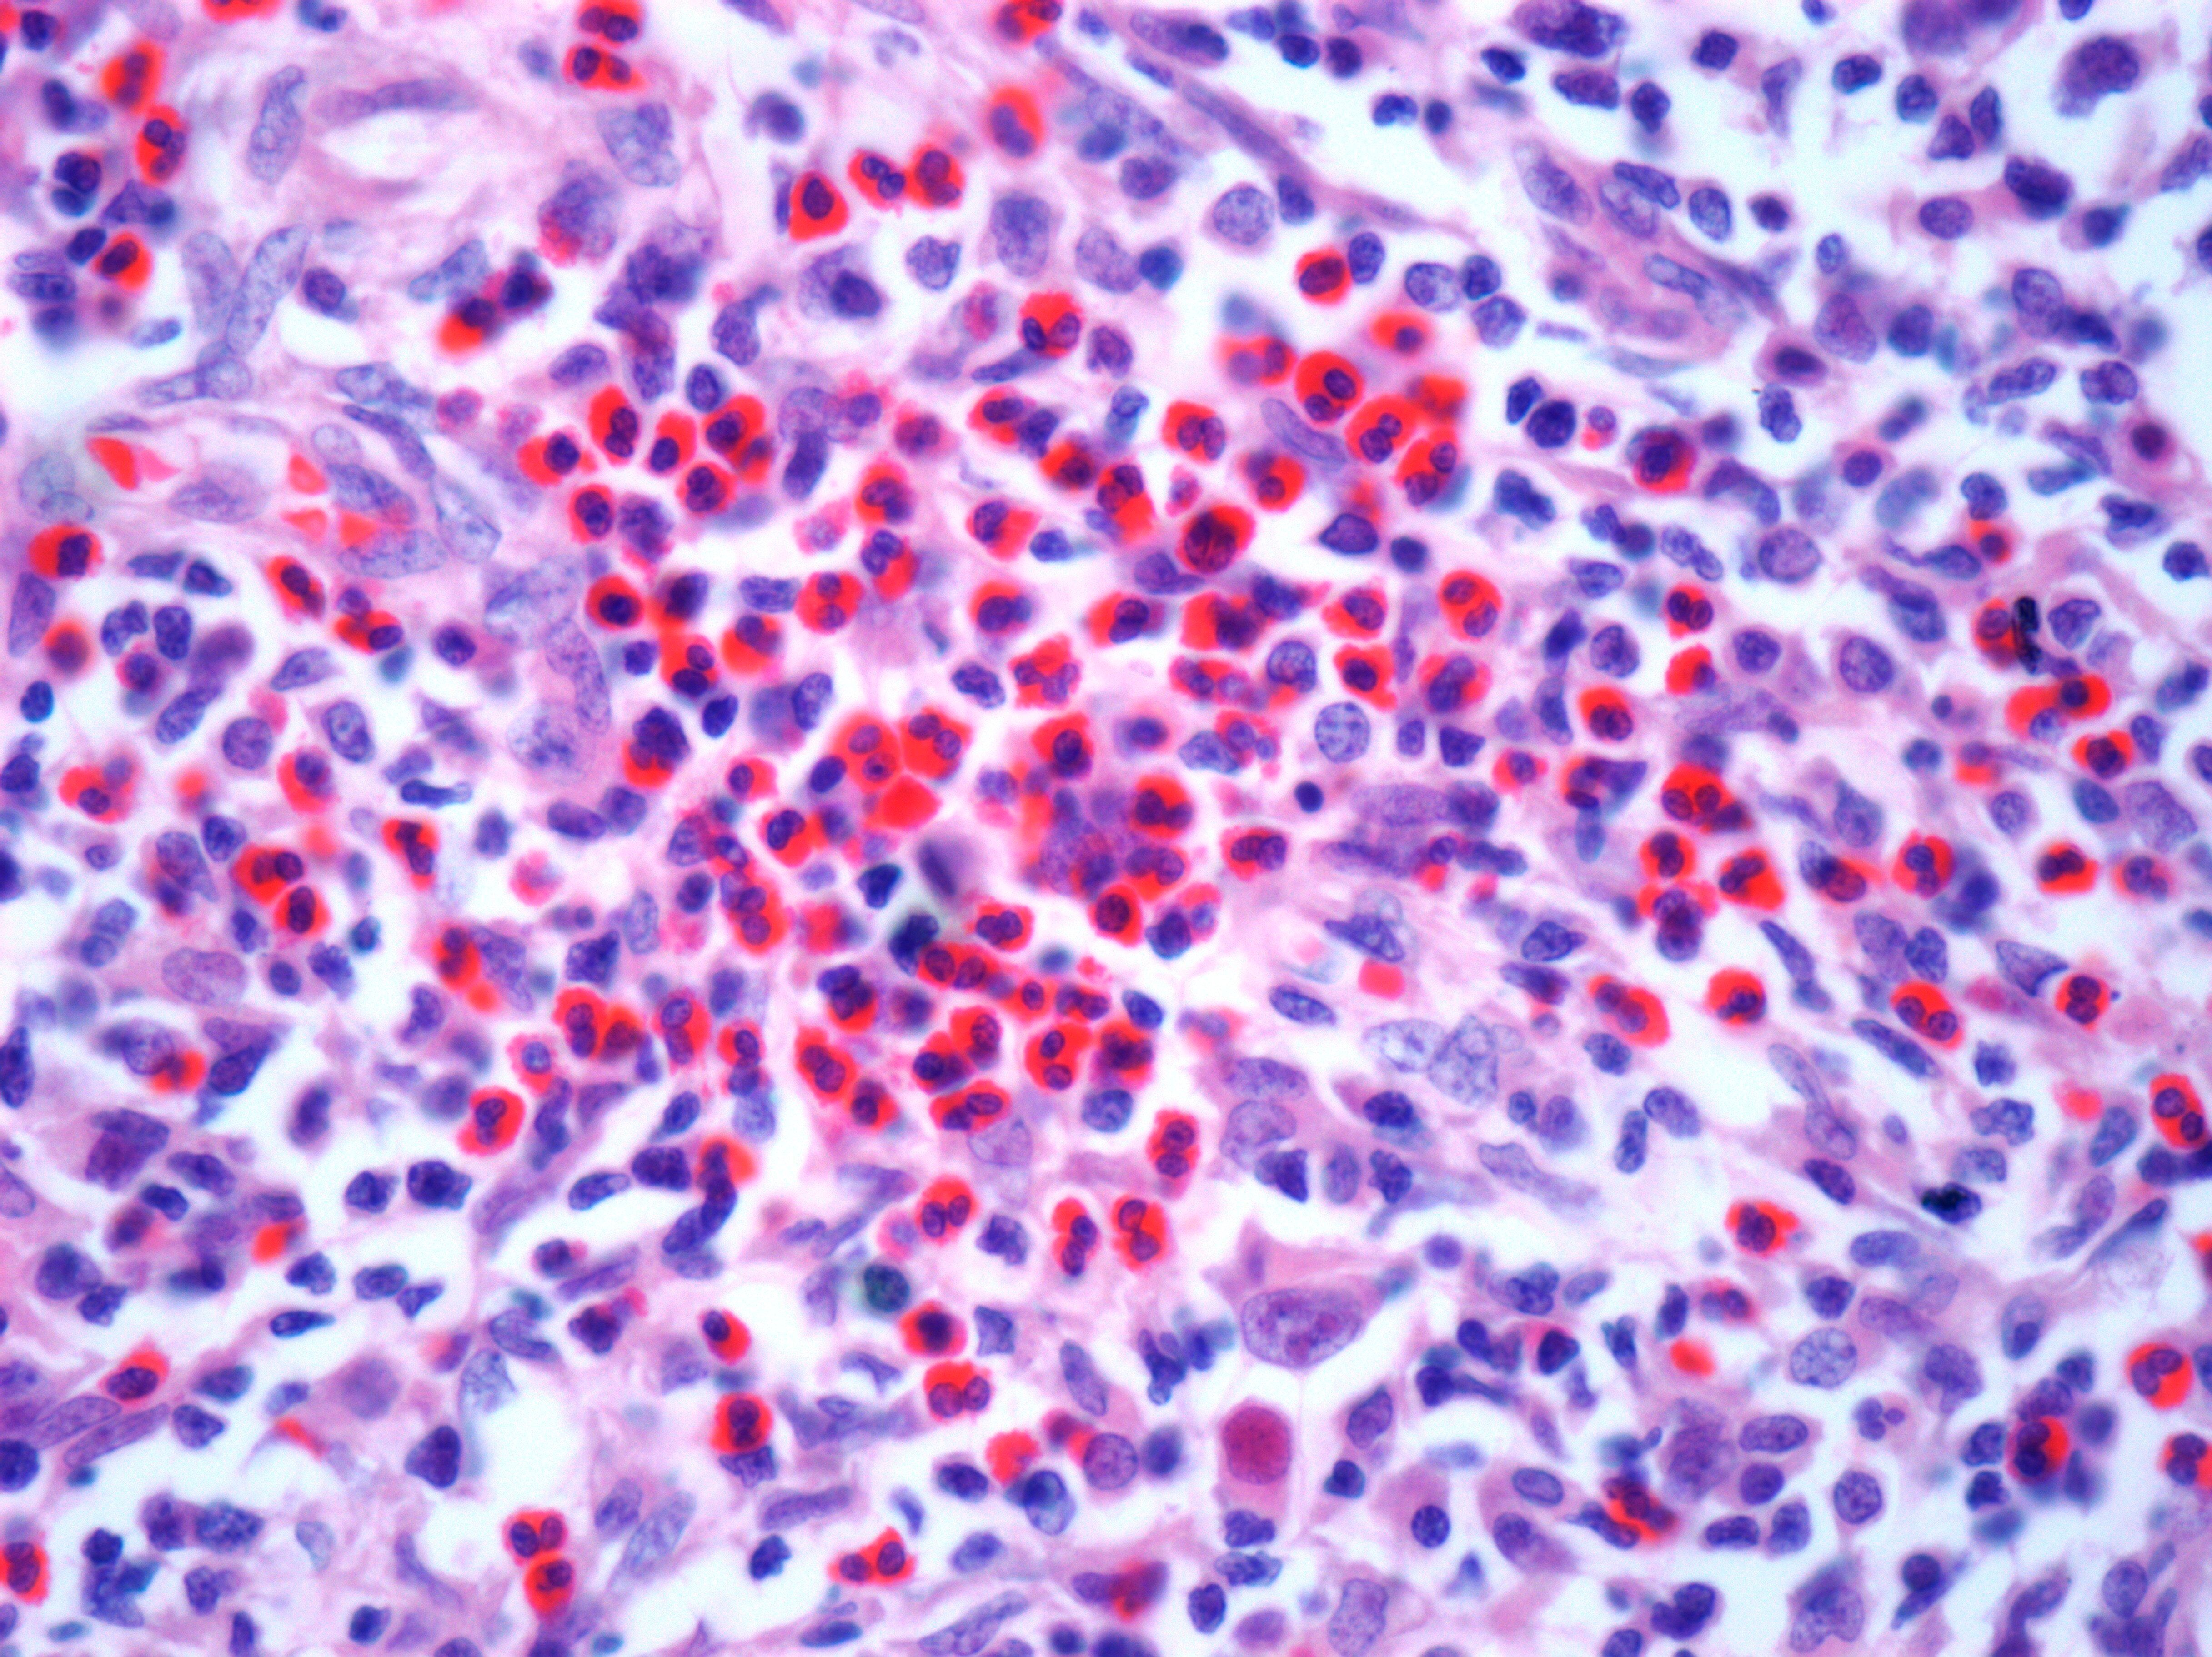

The TME is a complex and dense battleground of non-cancerous cells, signal molecules and structural components that surround and interact with the tumour. It includes immune cells such as macrophages and T cells, as well as stromal cells like cancer-associated fibroblasts (3). A major barrier to successful tumour immunology based treatment is the immunosuppressive TME which contains cells, signals and conditions that restrain the anti-tumour response. The TME facilitates immune evasion through an enrichment of regulatory T cells and M2 macrophages, which can inhibit effector immune cells and secrete immunosuppressive cytokines, including, IL-10 and TGF-B (4). Upregulation of checkpoint proteins like PD-L1 on tumour cells is another cancer escape mechanism used in the TME (3). Immunotherapies like immune checkpoint inhibitors, and CAR T cell therapy, aim to reinvigorate anti-tumour responses to overcome immunosuppression in the TME. Additionally, immune filtration can be an issue due to the increased extracellular matrix in the TME, leading to ‘cold’ tumours (3). As the TME’s immune evasion and immunosuppression is such a significant obstacle to immunotherapies, there is a need to elucidate the mechanisms of action in the TME.

Immunotherapies take aim at tumours by harnessing the immune system’s power, but many malignancies reside in immune blind spots, escaping detection. ‘Cold’ tumours occupy these blind spots, as these tumours lack typical immune cell infiltration and inflammation. These ‘cold’ tumours also tend to have a lower mutational burden and display fewer tumour specific antigens (6). Because of the lack of tumour antigens, T-cells are not primed and activated and therefore, do not infiltrate into the TME. Checkpoint inhibitors work by blocking inhibitory signals on T cells, if no T cells are present due to lack of activation, checkpoint inhibitors have no T cells to target. To tackle these ‘cold’ tumours with modern immunotherapies, we need to turn ‘cold’ tumours ‘hot’. Some potential tactics include combination therapies integrating epigenetic modulators like HDAC inhibitors, which can upregulate MHC class I and II expression on tumour cells, making them better targets for T cells (7). HDAC inhibitors have also been shown to shift tumour-associated macrophages from an M2 immunosuppressive to an M1 inflammatory subtype (8). Traditional oncological treatments, like radiotherapy, can also play a role in facilitating the conversion of cold to hot tumours; for example, after radiotherapy, endothelial cells express molecules like ICAM1 which facilitates the attraction of immune cells (9). Encouraging the infiltration of immune cells into cold tumours, could help tip the balance in favour of the immune system, leading to the eradication of tumours.